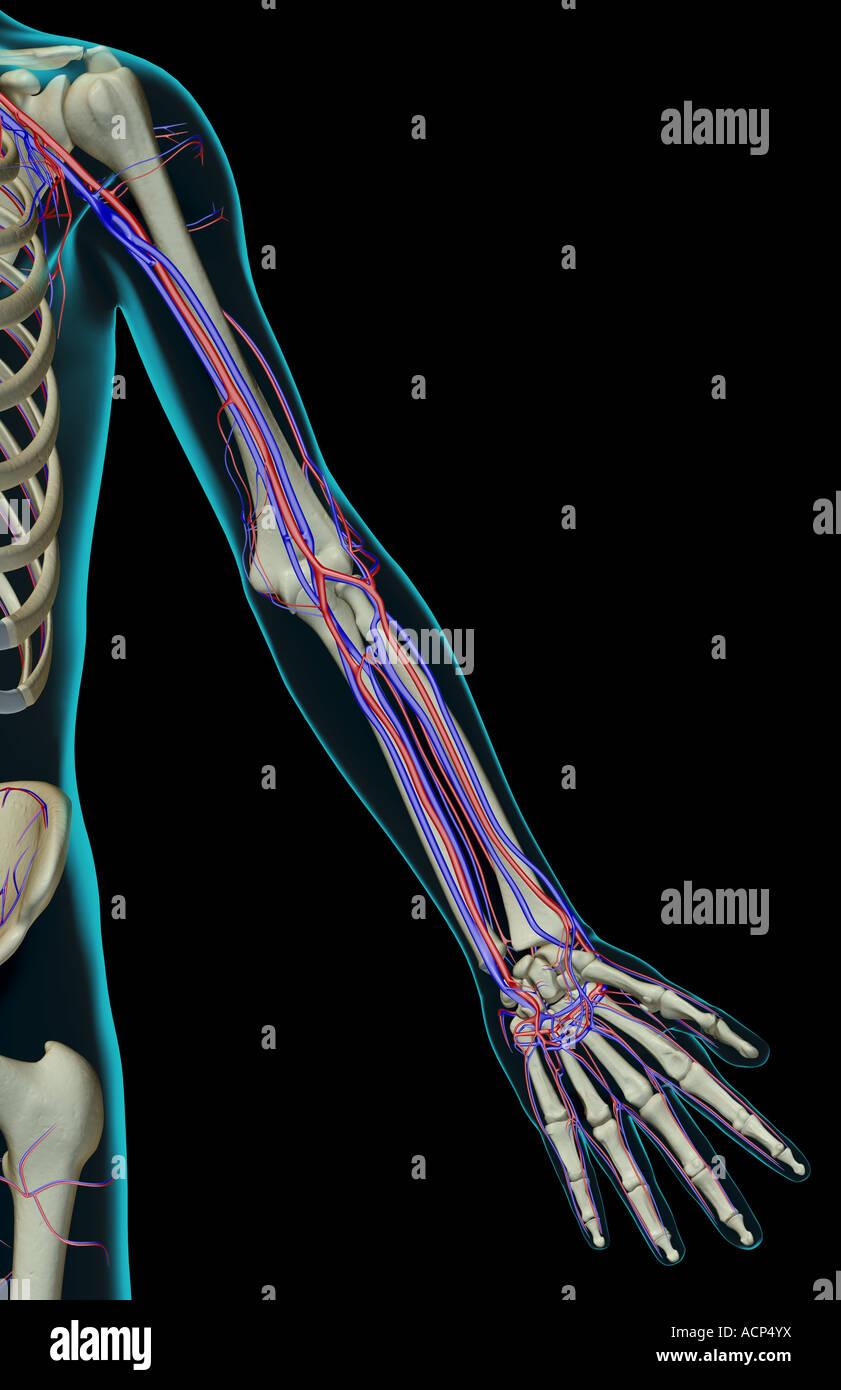

The blood supply of the upper limb Stock Photohttps://www.alamy.com/image-license-details/?v=1https://www.alamy.com/stock-photo-the-blood-supply-of-the-upper-limb-13204237.html

The blood supply of the upper limb Stock Photohttps://www.alamy.com/image-license-details/?v=1https://www.alamy.com/stock-photo-the-blood-supply-of-the-upper-limb-13204237.htmlRFACP4YX–The blood supply of the upper limb